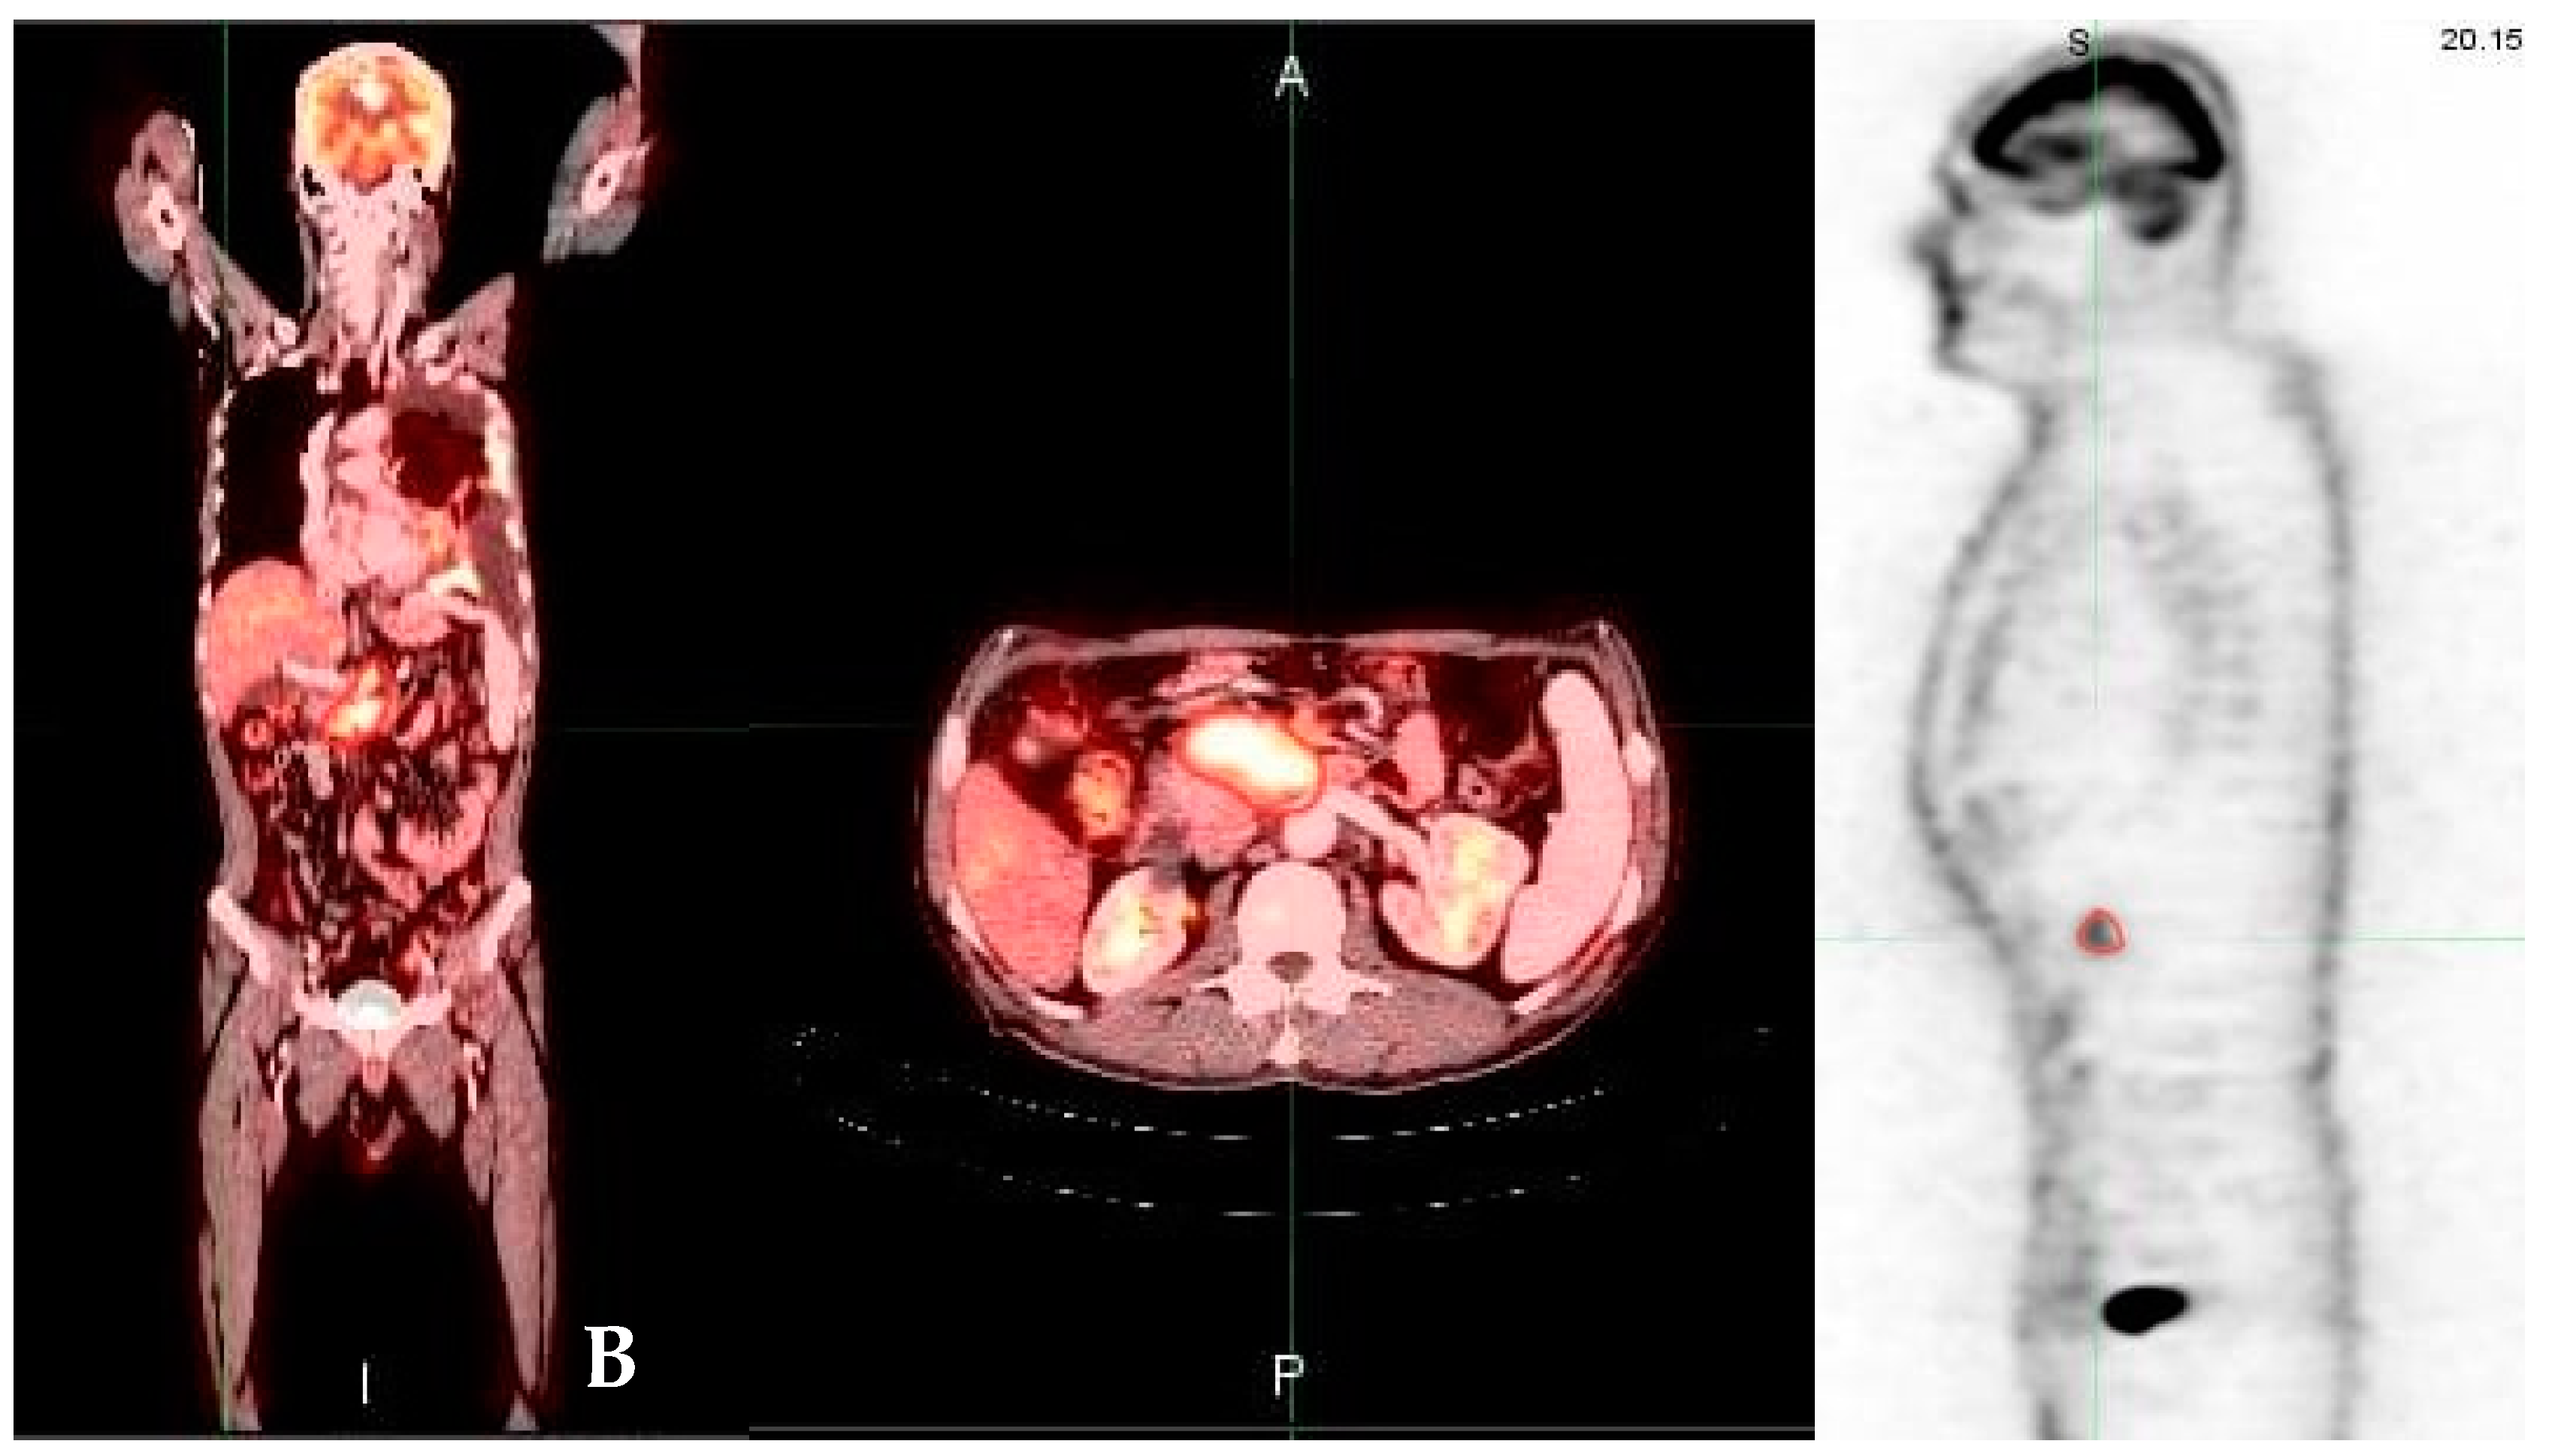

3.2. FDG PET/CT Parameters Results

3.3. Tumor Glycolytic Activity

3.4. Relationship to Survival